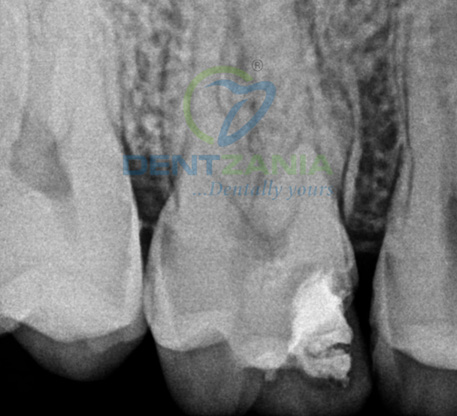

1. Diagnosis & X-Ray

X-rays are taken to assess the damage

Before / After